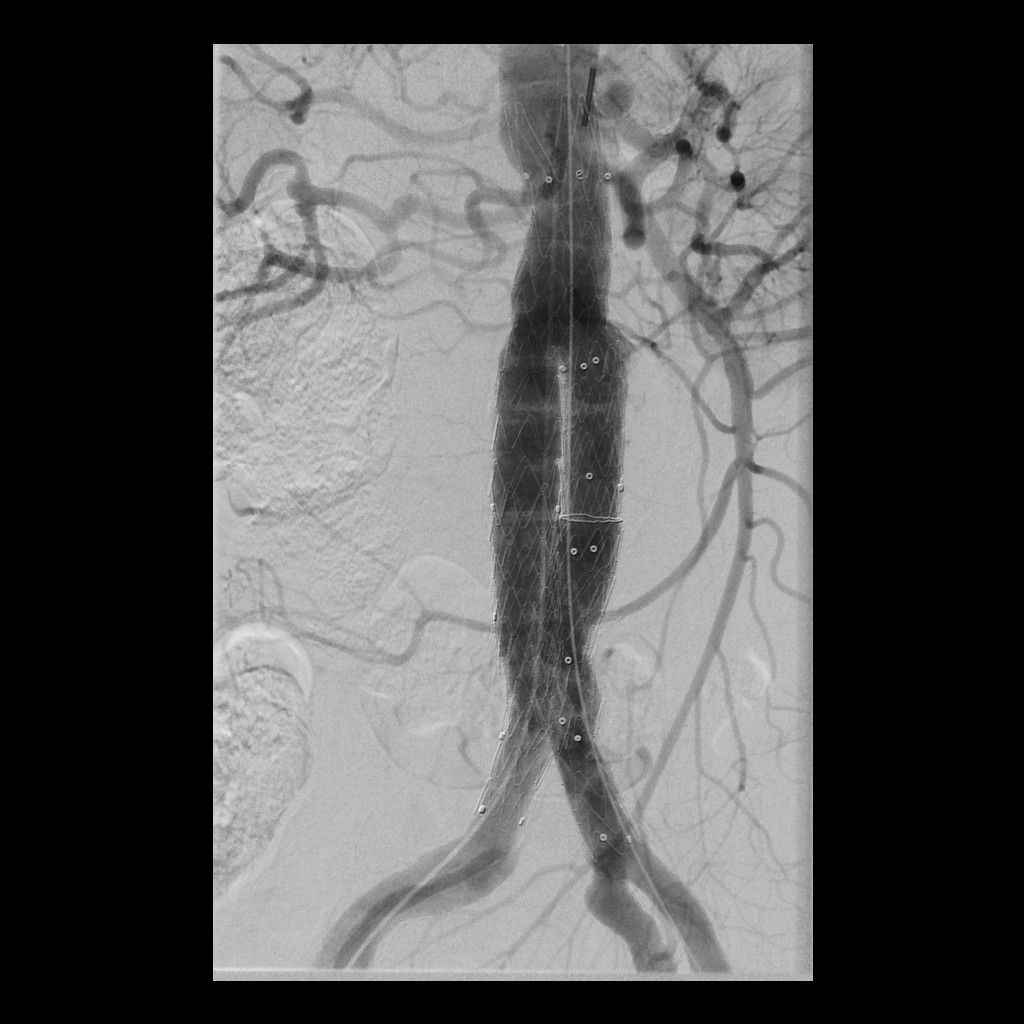

Eine Erweiterung der Bauchschlagader kann das Risiko eines Gefäßeinrisses stark erhöhen (Aneurysma). Die Radiologie bietet hier zusammen mit den Kollegen der Gefäßchirurgie ein minimal-invasives Verfahren zur Ausschaltung des Aneurysmas an. Dies geschieht mittels Stent-Prothese (endovascular aortic repair; EVAR).